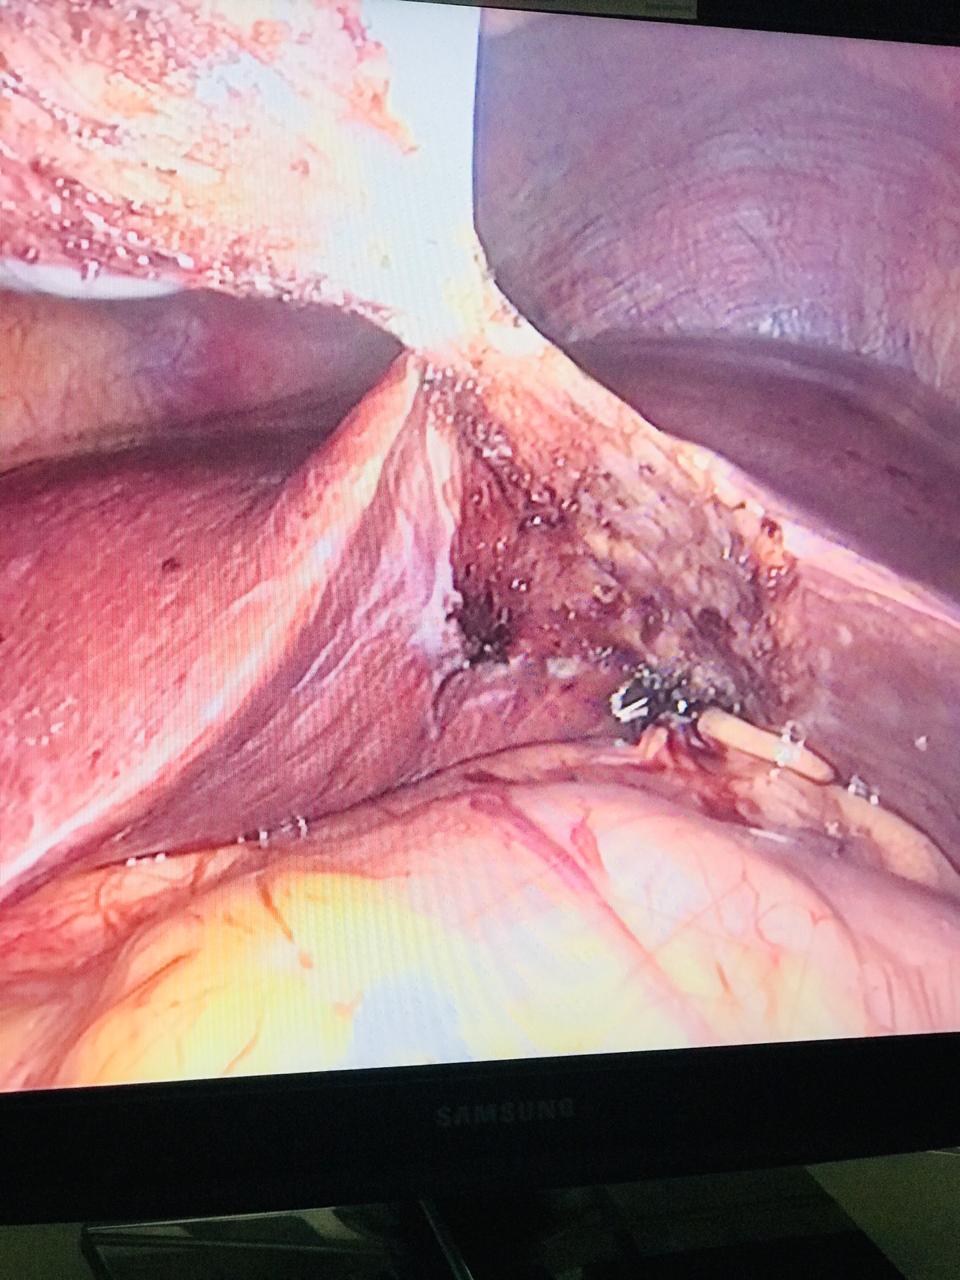

Gallbladder cancer is most common in people who have gallstones or have had gallstones in the past. Larger gallstones may carry a larger risk. Still, gallstones are very common and even in people with this condition, gallbladder cancer is very rare. Other gallbladder diseases and conditions